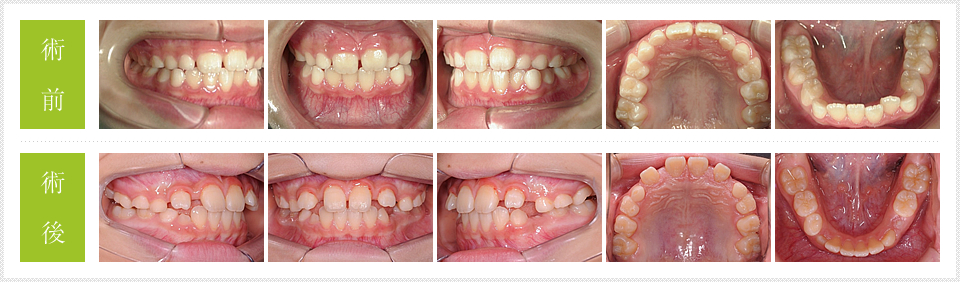

口の中の写真を見ると術前の方がきれいに並んでいるように見えますが、歯のレントゲンで確認すると左右の犬歯が生えるスペースが全くなく、このままでは完全に八重歯になってしまいます。術後の写真は上の前歯が開いているよう見えますが、左右の犬歯が出てくるときに2番目の歯を真ん中に寄せながら生えてくるので今の段階ではこれでいいのです。この段階から順次、歯が生えて行くのを観察するのです。